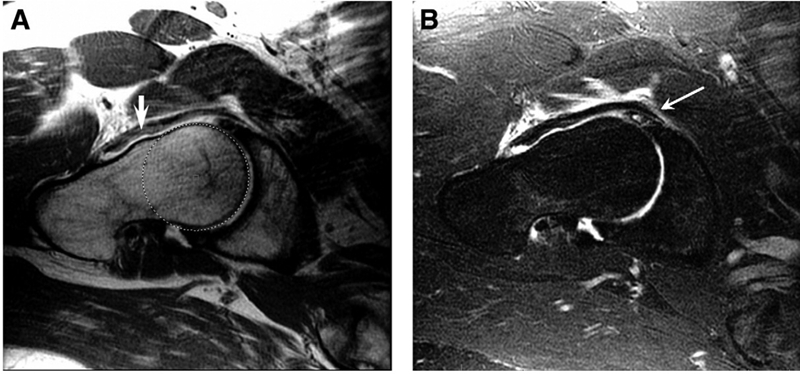

图1.盂唇撕裂经常与凸轮撞击有关,如这些T1和T2加权MRI扫描所示。

(A)股骨头颈交界处的偏移量和非球面度(圆形)增加,导致头颈交界处出现特征性的骨“隆起”(粗箭头),如T1图像所示。(B)在同一患者的T2加权图像中显示了前头颈交界处的盂唇病变(更长的细箭头)。